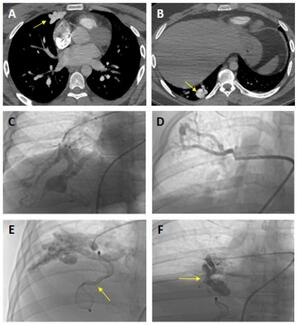

A 27-year-old man presented to the emergency department with complaints of syncope, dyspnea, and fatigue. Physical examination revealed left-sided mild hemiparesis, platypnea, and continuous murmur on right middle lobe lung auscultation.